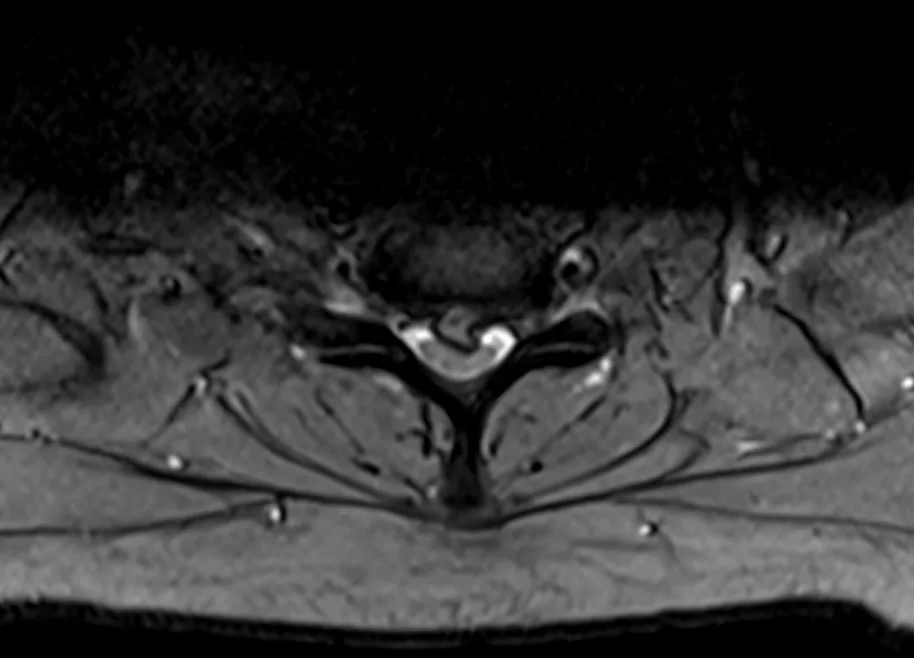

Ασθενής γυναίκα 57 ετών με αιμωδίες αριστερού άνω άκρου, αυχεναλγία και διαταραχή βάδισης.

Ο απεικονιστικός έλεγχος έλεγχος με μαγνητική και αξονική τομογραφία της αυχενικής μοίρας της σπονδυλικής στήλης ανέδειξε σημαντική εκφύλιση της αυχενικής μοίρας της σπονδυλικής στήλης με πολυεπίπεδη στένωση λόγω εκτεταμένης οστεφύτωσης και επασβέστωσης του οπισθίου επιμήκους συνδέσμου.